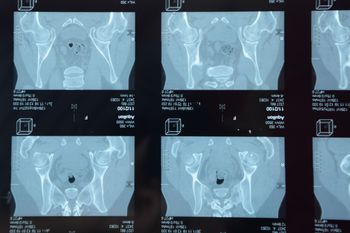

Total hip arthroplasty does not provide a clinically significant improvement over hemiarthroplasty in function and quality of life over 24 months, shows a NEJM study. The incidence of secondary procedures did not differ significantly between the two groups.

Social support may be a prognostic factor for some joint-specific and general health outcomes after hip or knee replacement, say researchers writing in The Lancet Rheumatology this month.